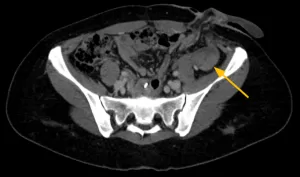

Imagens-chave

Derivação urinária em alça delgada na fossa ilíaca à esquerda. Houve boa distensão da alça de derivação, porém nota-se falha de enchimento de aspecto polipoide na fase excretora medindo cerca de 2,2 x 1,0 cm. Sugere-se prosseguir investigação.

• Lesão polipoide na alça ileal da derivação urinária

Estudo endoscópico